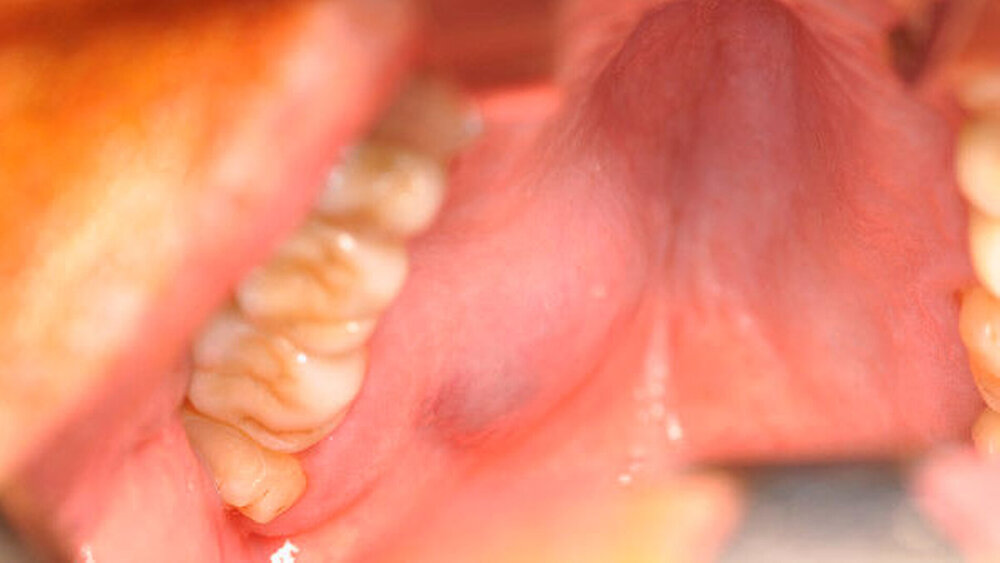

Ein 53-jähiger Patient stellte sich nach der Überweisung durch seinen Hauszahnarzt mit einer umschriebenen Schwellung im Bereich des Hart- und Weichgaumens rechts in der Poliklinik der Mund-, Kiefer- und Gesichtschirurgie der Universitätsmedizin Rostock vor. Klinisch imponierte eine blau- livide, submuköse palatinale Raumforderung, die weder druckdolent noch verschiebbar war (Abbildung 1). Anamnestisch war es während der vergangenen Wochen bis Monate zu einem leicht progredienten Wachstum gekommen. Weitere Erkrankungen verneinte der Patient.

Superfizial-submuköse Läsionen zeigen oft eine bläulich-rote Farbe und somit Ähnlichkeiten zu Mukozelen beziehungsweise vaskulären Läsionen. Die Diagnose wird histologisch nach einer Feinnadel- oder einer Exzisionsbiopsie getroffen, wobei beim Mukoepidermoidkarzinom muköse, mucin-positive und intermediäre Zellen in festem und zystischem Gewebe vorliegen [Kumar und Kämmerer, 2013]. Insbesondere müssen weitere maligne oder odontogene Tumoren ausgeschlossen werden.